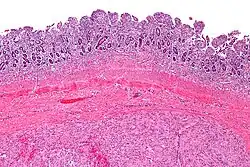

Mikroskopowo guz jest zlokalizowany w ścianie przewodu pokarmowego w obrębie mięśniówki właściwej (błona mięśniowa)[21]. Może szerzyć się w kierunku błony śluzowej i przekraczać blaszkę mięśniową błony śluzowej lub wzrastać w kierunku błony surowiczej (surowicówki)[22]. Utkanie może być od skąpokomórkowego do bogatokomórkowego[23], przy czym zwykle jest bogatokomórkowe[22]. Nowotwory stromalne charakteryzują się niskim pleomorfizmem i niewielką aktywnością mitotyczną, figury mitotyczne są rzadkie i dotyczą jedynie guzów o wysokiej złośliwości i odróżnicowanych[23]. Utkanie nowotworu budują komórki wrzecionowate przeważające w 70% przypadków GIST i komórki nabłonkowate (epitelioidne) przeważające w 20% przypadków GIST. W około 10% guzów stwierdza się utkanie mieszane[23].

Komórki wrzecionowate cechują się bladą cytoplazmą i wydłużonym jądrem komórkowym z ostro zakończonymi brzegami. Komórki są stosunkowo jednolite, ułożone w pęczki i arkusze, czasem tworzą struktury wirowate[23][22]. Zrąb jest ubogi[12].

Komórki nabłonkowate przyjmują kształt okrągły, o eozynofilnej lub jasnej cytoplazmie z okrągłym lub owalnym jądrem. Komórki są ułożone w struktury gniazdowate lub pasmowato[23][22][12].